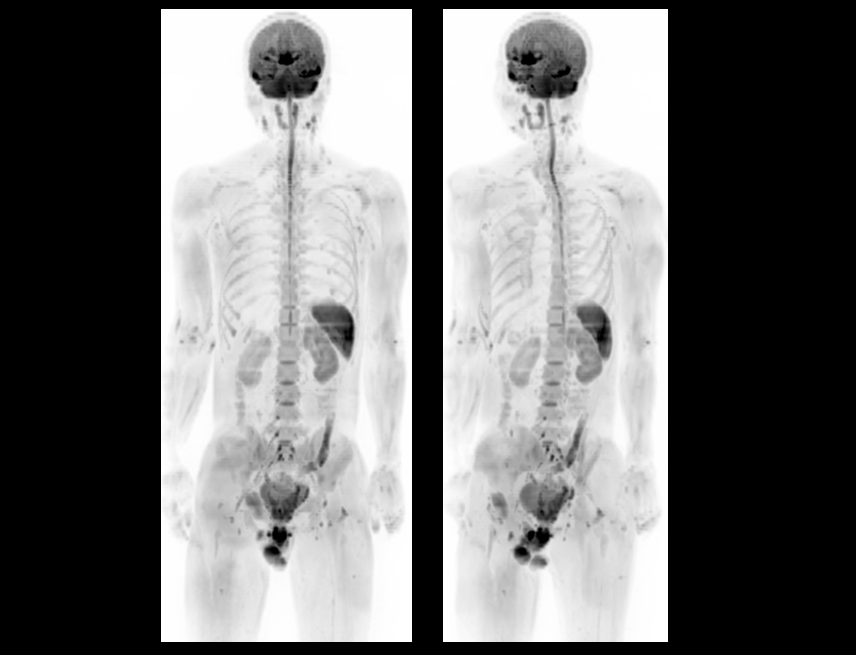

Boundless Clinical Scenarios

uMR Omega™은 uAIFI 기술 플랫폼의 지원을 받아, 상당한 성능 향상, 강력한 이미징 능력, 개선된 작업 흐름 및 향상된 사용자 경험을 통해 많은 기대를 받고 있습니다.

Greater Access for Your Community

75cm 초광경.

310kg의 테이블 하중 수용력.